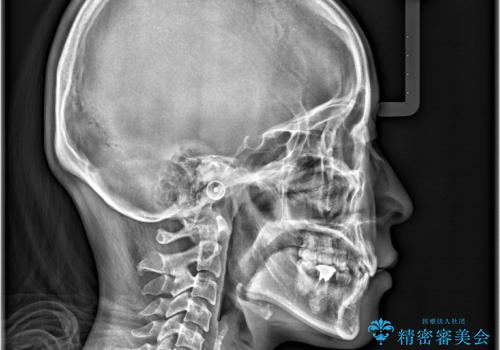

- 「歯のデコボコ、八重歯、口ボコが気になる」を主訴に来院された患者様です。

上下左右4番(4本)の歯を抜歯しワイヤー矯正で治療を行いました。

計4本の抜歯を行い、歯のデコボコと口元がすっきりし、大変ご満足していただけました。